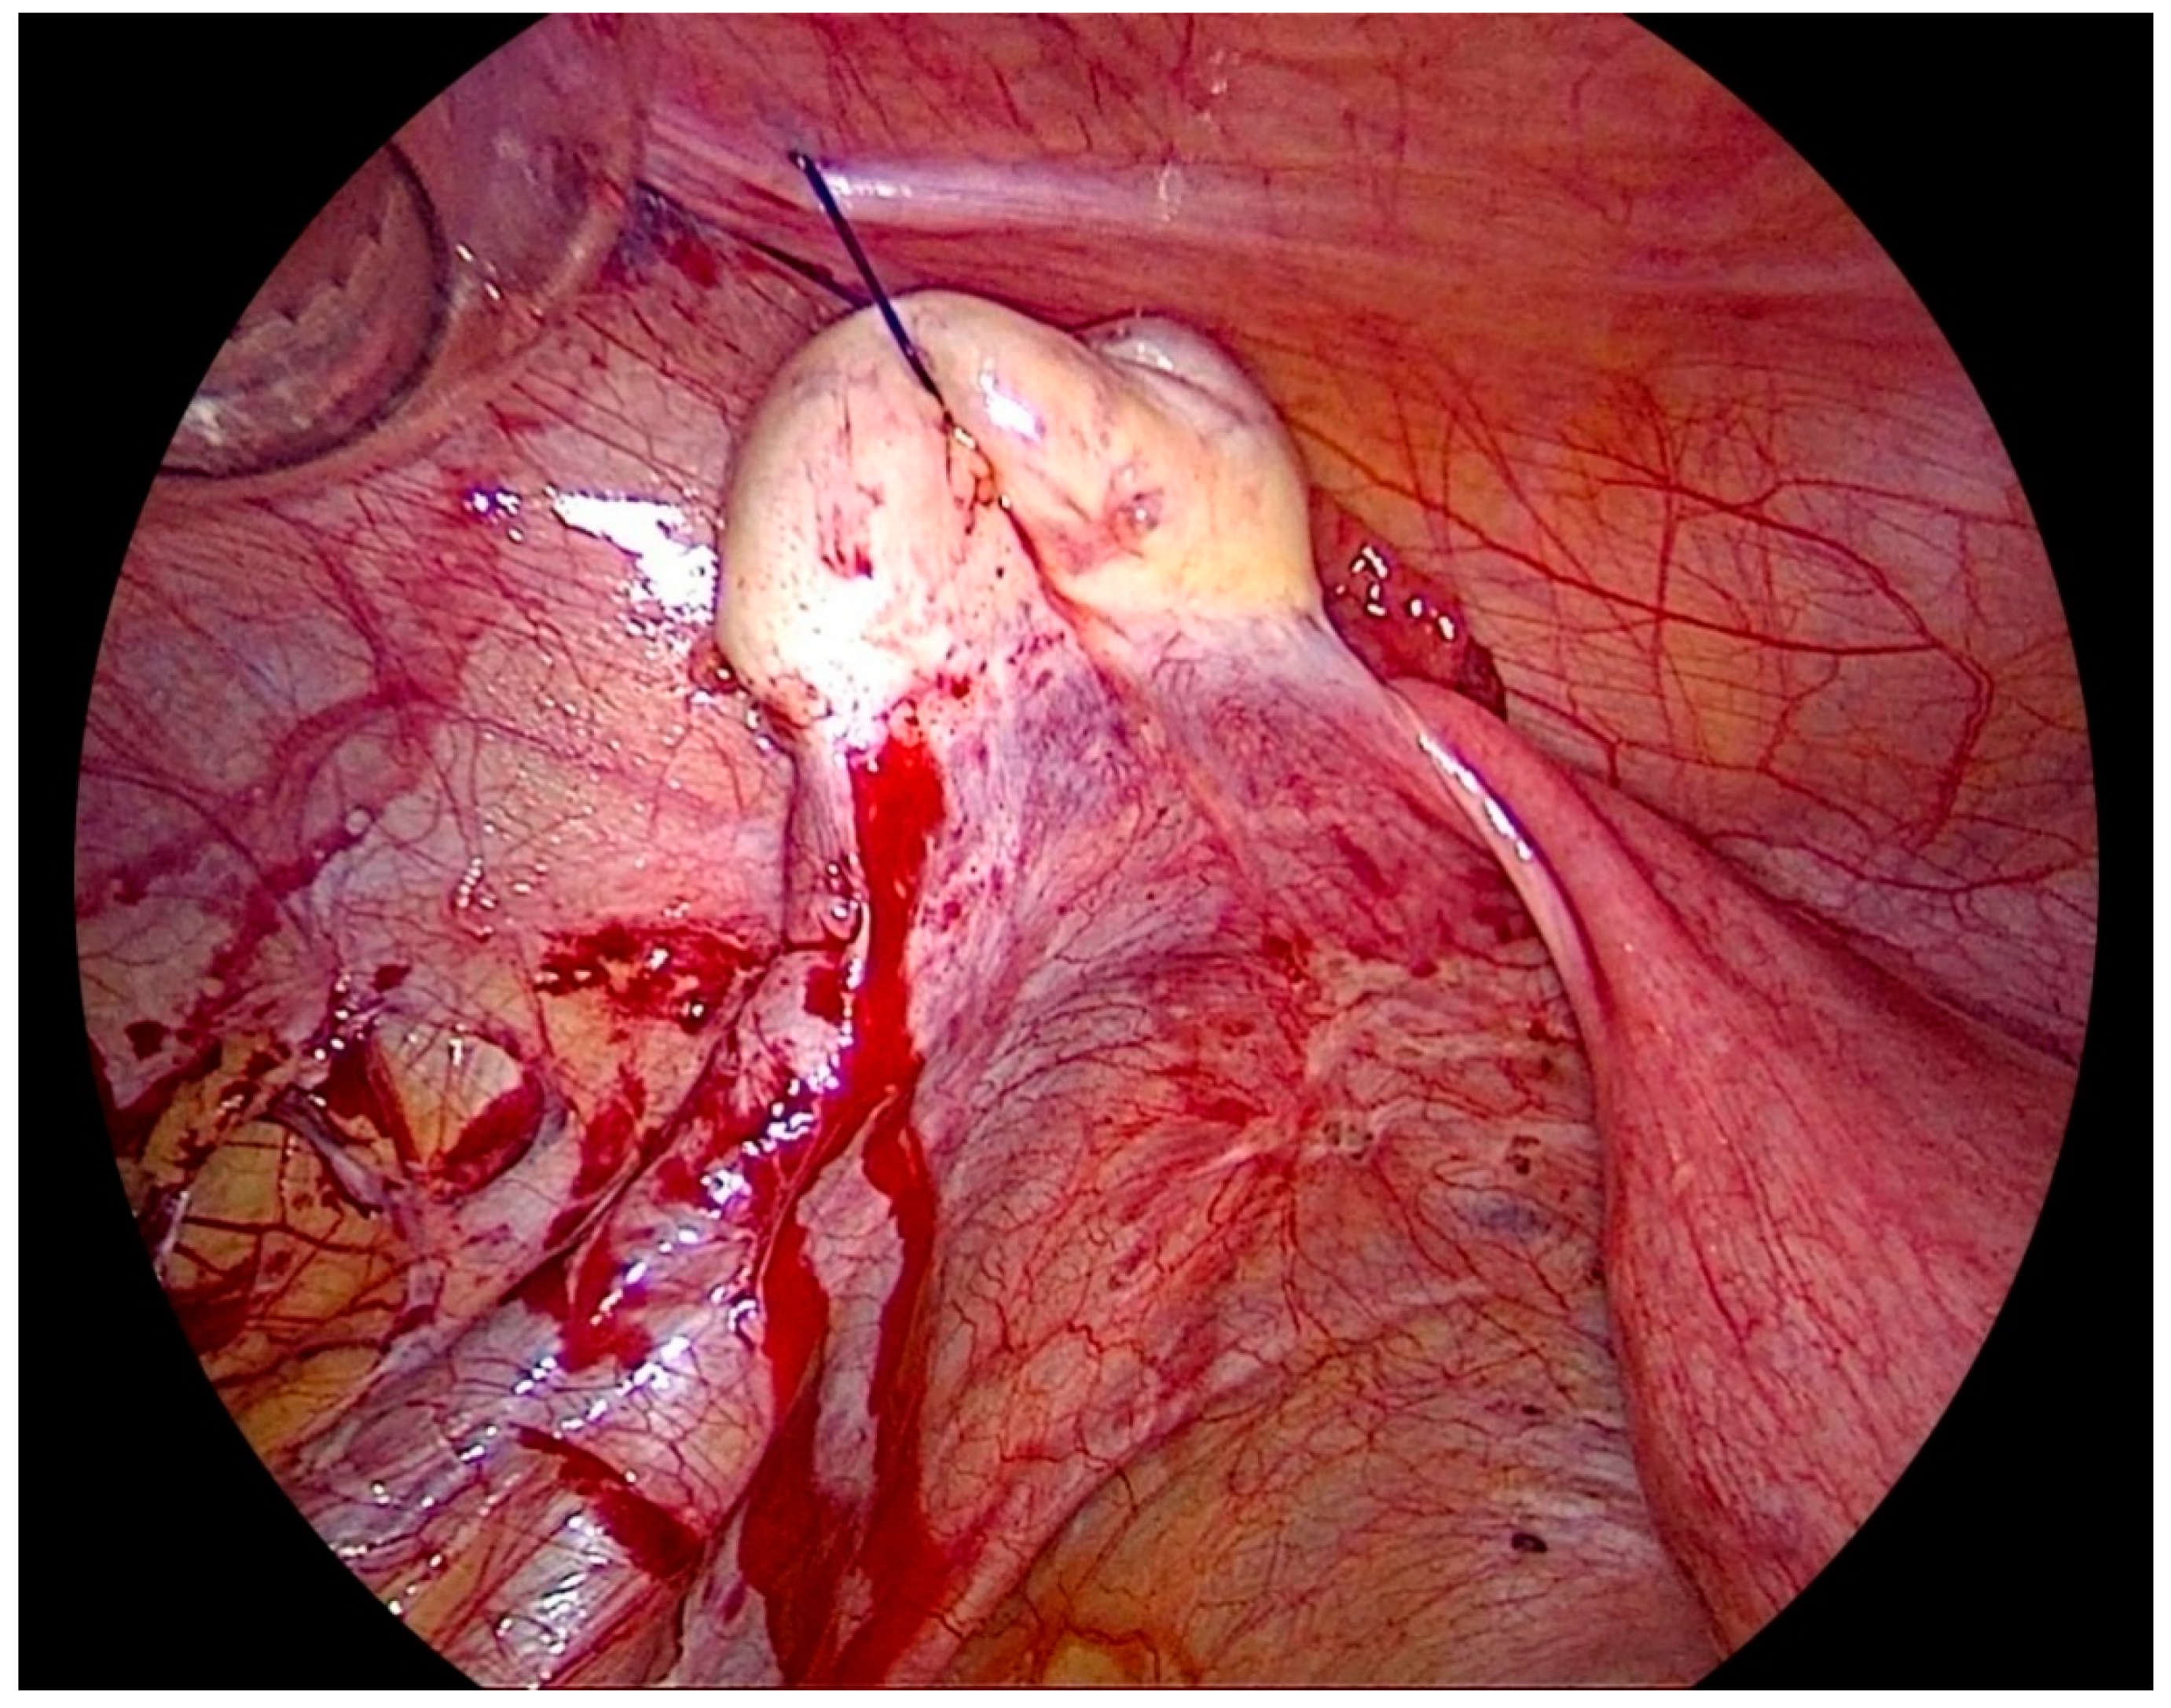

Figure 2.

Laparoscopic view of the lateral pelvic wall on the left side after ovariopexy with endometriosis easily visualized and accessible.

After the procedure is complete, the ovarian suspension is loosened to maintain a gap of 1–2 cm between the ovary and the abdominal wall to prevent adhesions. This suspension is maintained for 5 days, and sutures are cut on the day 5th-day post-surgery (Figure 3).

Figure 3.

Left side ovary suspended to the anterior abdominal wall, with dissection of the left lateral pelvic wall.